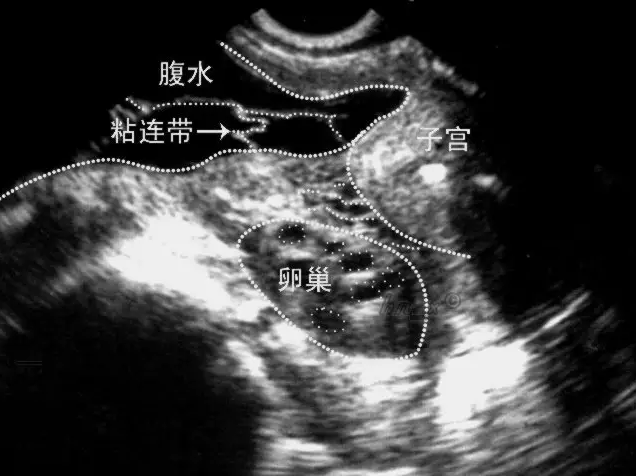

盆腔黏连主要是指盆腔内的组织出现了细菌感染或者病毒感染,从而导致组织器官出现了炎症的现象,由于盆腔黏连的出现,很有可能会导致患者出现子宫输卵管炎,卵巢炎等等问题,由于这些疾病的原因,就有可能会导致患者的身体症状出现,比如患者可能会出现水肿,分泌物增多等等问题,如果不及时的进行控制,还有可能会诱发其他问题的出现,如影响输卵管蠕动和绒毛摆动,无法正常拾卵,影响女性怀孕。